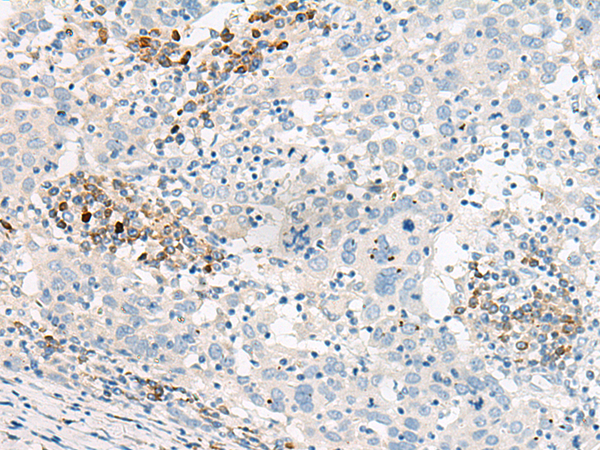

IHC positive control:

Human cervical cancer

IHC Recommend dilution:

30-150